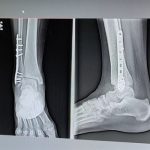

PIONEER MEDICAL AND PARAMEDICAL CAMPUS ORGANIZED ARTHRITIS CHECK UP AND LAB TEST CAMP AT PIONEER HOMOEOPATHIC HOSPITAL ON 20,22 & 24TH DEC 2021 IN LIEU OF AZADI KA AMRIT MAHOTSAV TO SPREAD AWARENESS ABOUT ALTERNATIVE MEDICINES.  IN CAMP PATIENTS WERE OFFERED VARIOUS LAB TESTS AND RADIO-LOGICAL INVESTIGATIONS AT DISCOUNTED RATE & GIVEN FREE HOMOEOPATHIC CONSULTING AND MEDICINE FOR 15 DAYS WITH GUIDANCE AND REFERRAL TO PHYSIOTHERAPY AND AYURVEDA THERAPIES IN CO-ORDINATION WITH HOMOEOPATHIC TREATMENT ON DISCOUNTED RATES. WE ARE THANKFUL TO DR. PRANAV PATEL [M.S. ORTHO] SIR FOR THEIR GUIDANCE AND HELP IN DIAGNOSIS OF ORTHOPEDIC CASES AND WILLINGNESS TO OFFER DISCOUNTED RATE IN SURGERIES WITH CO-OPERATION OF PIONEER MEDICAL CAMPUS. WE ARE THANKFUL TO DR. LIPIKA CHAKRABORTY [M.D. HOMEO] MADAM FOR THEIR SERVICE IN HOMOEOPATHIC COUNSELLING AND CONSULTING OF PATIENTS. WE ARE THANKFUL TO AYURVEDA AND PHYSIOTHERAPY DEPARTMENTS TO CO-OPERATE WITH HOMOEOPATHIC HOSPITAL TO MAKE THIS MEGA EVENT A SUCCESS.